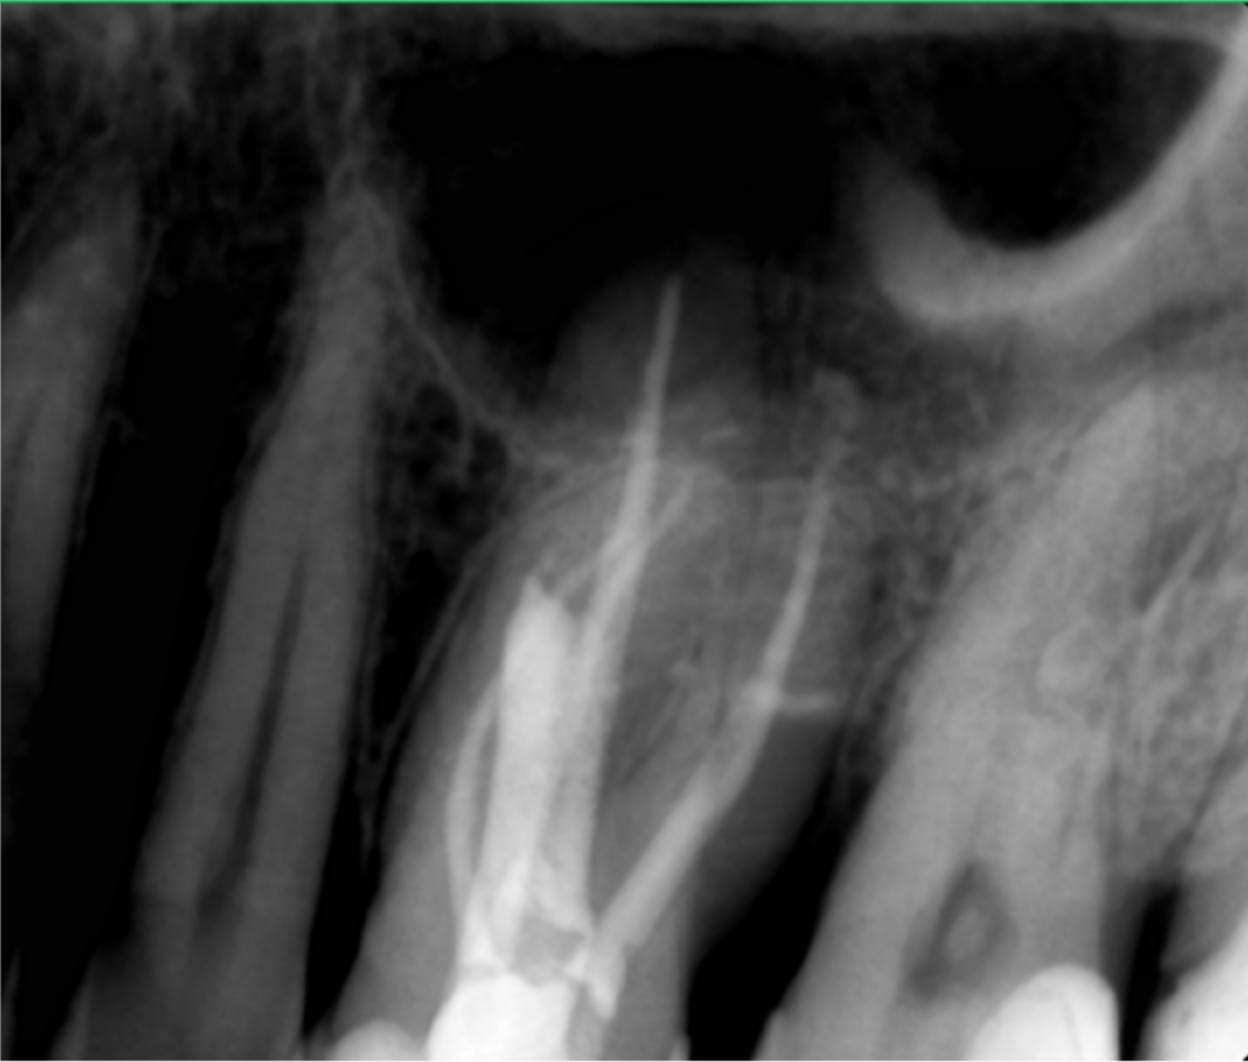

Ulterior, indepartam fragmentul de ac cu ajutorul unui lasou endodontic (fig 4, 5).

In aceasta situatie, am retratat dintele integral, incepand cu refacerea tratamentului pre-endodontic, iar dupa ce am instrumentat si canalul MV2, am inchis perforatia preexistenta cu ajutorul unei bioceramici de consistenta chitoasa. (fig. 6)